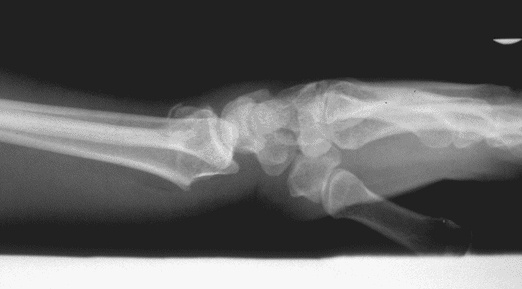

Case 1 Injury